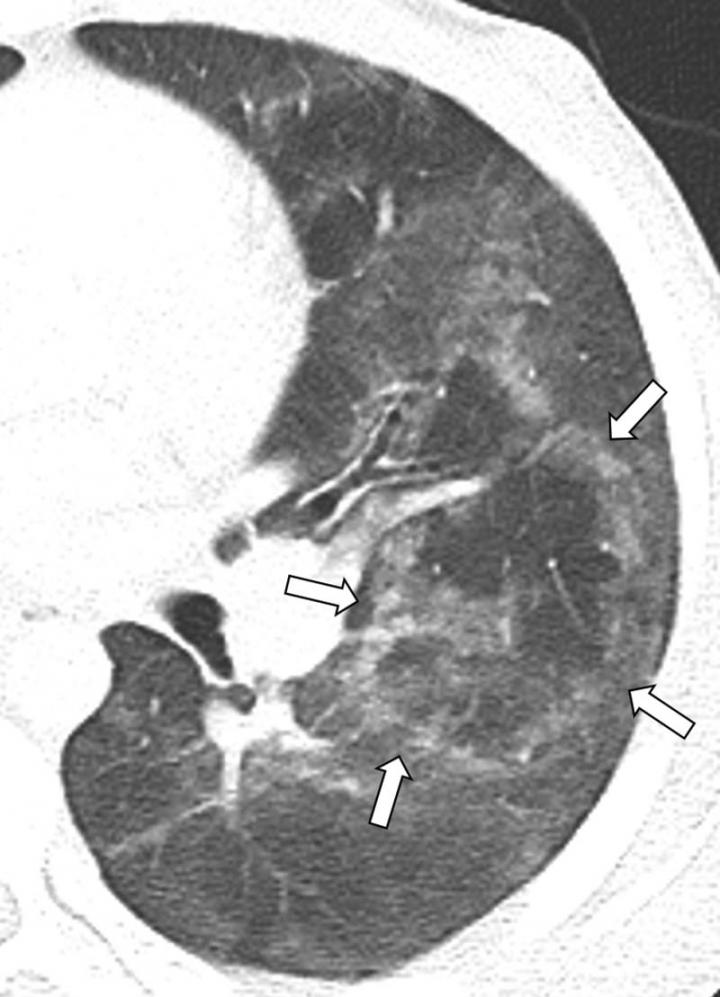

The results showed characteristic chest X-ray and CT findings. Bilateral and symmetric ground-glass opacity in the lungs, frequently associated with consolidation, often of lower lobe predominance, was the key imaging finding. On CT, subpleural sparing was also visualized in 79% of patients.

"Another imaging feature observed on CT in 36% of our pediatric patients with EVALI, was the reversed halo sign, which is characterized by the presence of a central ground-glass opacity surrounded by denser consolidation of crescentic shape or complete ring," Dr. Artunduaga said.